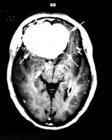

5、颅内肿瘤特别是蝶鞍区占位性病变,早期可呈球后视神经炎改变,视野及头颅X线有助诊断,头颅CT及MRI更有助于早期发现。

4、头颅CT,MRI检查等。